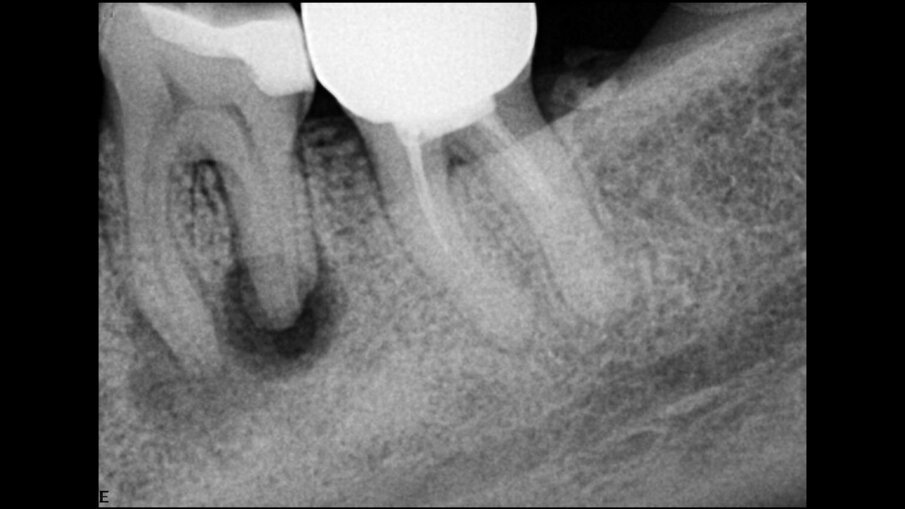

Počevši od dijagnostičkog dela, 3D snimanje je osnovni alat za kompletiranje zagonetke i pronalaženje odgovora, kao i za pripremu potpunog plana lečenja, kako za svaki jednostavan tako i za komplikovane slučajeve. Veštačka inteligencija (AI) je odličan dodatak u pogledu 3D snimanja. Već neko vreme koristim softver DTX Studio Clinic, koji ima mnoge funkcije veštačke inteligencije i poboljšane funkcije slike koje mi mnogo pomažu u svakodnevnoj praksi. Kada se kombinuje sa pravilnom rezolucijom i vidnim poljem za endodonciju, postaje veoma moćan dijagnostički alat. Nedavno smo nadogradili našu i-CAT jedinicu na DEXIS OP 3D jedinicu, koja ima mnogo prednosti u pogledu vidnog polja i kvaliteta slike, a savršena je kada se kombinuje sa DTX softverom. Digitalna 3D slika omogućava otkrivanje neuobičajene anatomije. U slučaju pacijenta koji se žalio na bol i pritisak na zub nakon što je neko vreme bio podvrgnut terapiji kanala korena, pažljivo čitanje CBCT skeniranog područja otkrilo je drugi kanal u centralnom sekutiću i omogućilo nam da lociramo furkaciju (Sl. 1–3).

Sl.1a i b: CBCT skeniranje koje pokazuje drugi kanal u centralnom sekutiću (E režim; vidno polje: 5 × 5 mm).

Figs. 1a & b: CBCT scan showing a second canal in the central incisor (E mode; field of view: 5 × 5 mm).